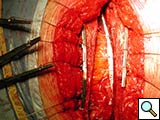

Figure 9. The device (constructed out of four units) is implanted, where the third clip is positioned corresponding to the fractured bone.

Indications for use have been prevention of sternal fracture after sternotomy in patients with severe osteoporosis, when a faulty sternotomy has been performed, in obese patients, or when additional risk factors for wound dehiscence are present. Molina, et al., and other authors have reported a high incidence of sternal dehiscence in obese patients [5]. We also use the device to stabilize the closure site when sternal fracture occurs intraoperatively or is detected postoperatively, requiring reoperation for sternal fixation (Figures 8-10).